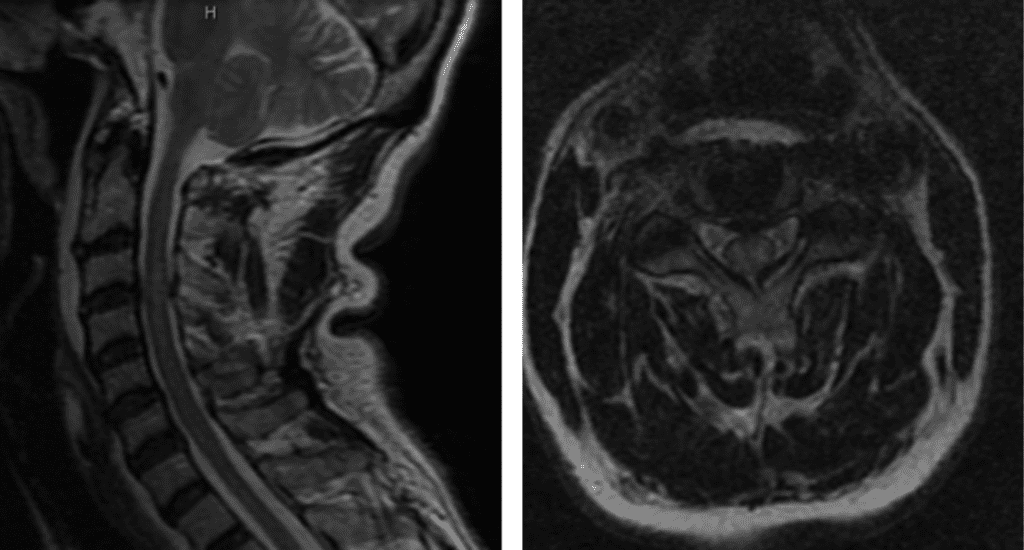

Figure 1. T2 MRI sagittal and axial showing C3/C4 disc herniation with compression of the spinal cord; spinal cord edema at the C3/C4 level.

This patient was suffering from compression of the cervical spinal cord. The fall caused an acute herniation of the cervical disc, which caused pressure on the spinal cord.

This particular spinal cord injury is called Central Cord Syndrome. This type of spinal cord injury typically affects the hands more than the legs and requires urgent surgical attention.